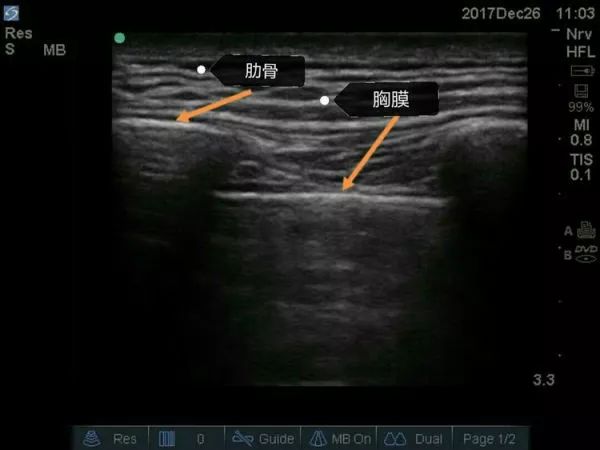

超声下肋骨及胸膜

左右横突中间的胸椎旁间隙